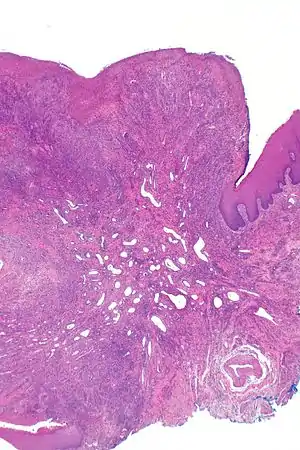

| Eosinophilic ulcer of the oral mucosa – H&E stain | |